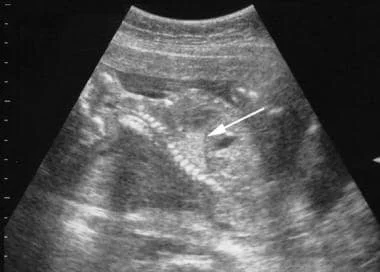

Ultrasound image showing a fetus with a congenital pulmonary airway malformation (CPAM).

An intralobar BPS lesion viewed on an ultrasound. The lesion appears brighter than the surrounding healthy lung tissue. Medscape article